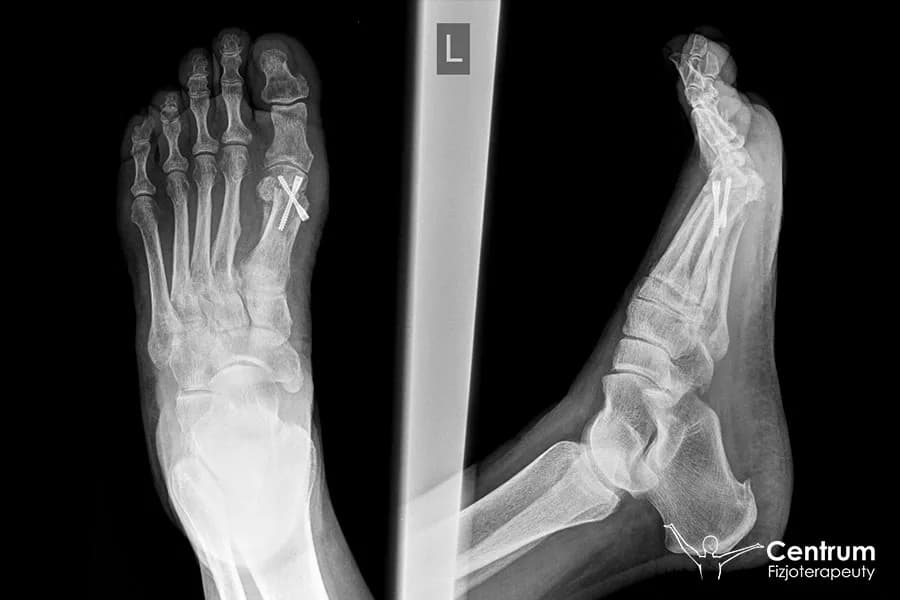

Ile trwa operacja haluksa? Poznaj szczegółowe ramy czasowe zabiegu, pobytu w szpitalu, rekonwalescencji i L4. Przygotuj się na powrót do sprawności!

Ból po operacji haluksa? Poznaj oś czasu rekonwalescencji, skuteczne metody łagodzenia bólu i dowiedz się, kiedy wrócisz do formy.